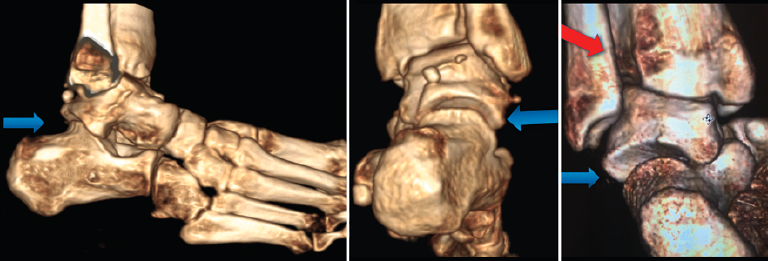

Figura 4. Secuencia volumétrica de posiciones del retropié en inversión y carga simulada en paciente diagnosticado de inestabilidad de tobillo. Nótese la descobertura subtalar (flecha azul) y la separación entre la tibia y el peroné (flecha roja).

En nuestra experiencia, tras el análisis de una serie de 72 pies y tobillos estudiados mediante la TC dinámica en carga simulada tanto en voluntarios sanos como en pacientes afectos de inestabilidad crónica de tobillo, se observó que existen diferencias significativas en el rango de movilidad rotacional a través de un eje helicoidal trazado en la articulación subastragalina a partir de las posiciones extremas en inversión y eversión subtalar (Figura 4). Manteniendo el astrágalo fijo en la mortaja tibioperonea con una dorsiflexión mantenida de 10°, el calcáneo viró en mayor grado a través de un eje helicoidal en los tobillos sintomáticos cuando se compararon con el tobillo contralateral asintomático (Figura 5). Asimismo, se observó una correlación entre variables de descobertura articular en la articulación subastragalina y calcaneocuboidea en las posiciones de máxima inversión del retropié y rotación interna (Figura 6).